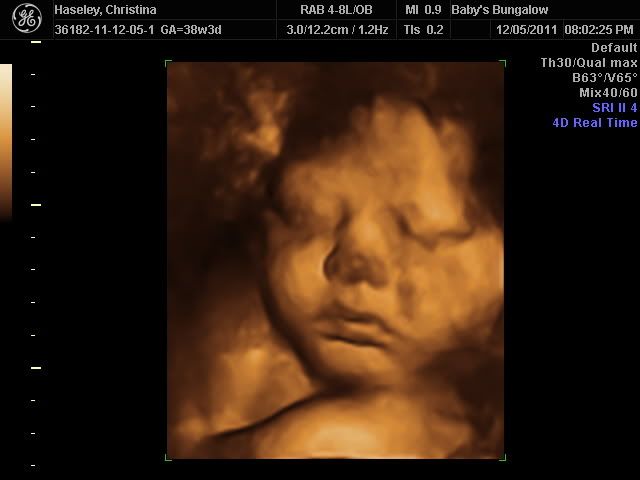

3d baby ultrasound photo: 3D Ultrasound in Buffalo, NY BabysBungalow4DVideos.jpg

The next day she had a scan because she started bleeding but said at this point she was ready to accept anything God wanted in her life. She later miscarried the baby in her home and said she was heartbroken but nonetheless felt she was fortunate to have met and held her little baby. She also added that she knew who had told her the truth about her baby because she could clearly see what a 12/14 week baby looked like now and he/she was just as the leaflet had described.

Not surprisingly, when the workers inside the clinic noticed the leaflet in the lady’s hand, they took it from her. They also told her that the image inside it of a 12 week baby (about the stage this mother was at) was a lie and that it wouldn’t look like that until at least 20 weeks. Of course, for the abortion centre, a mother changing her mind and choosing to keep her child means a loss in revenue so any helpful material is likely to be removed.

She wanted the pictures of her unborn baby published to encourage other women in crisis pregnancies. She said “I want my baby’s passing to help someone else realise how precious life is”.